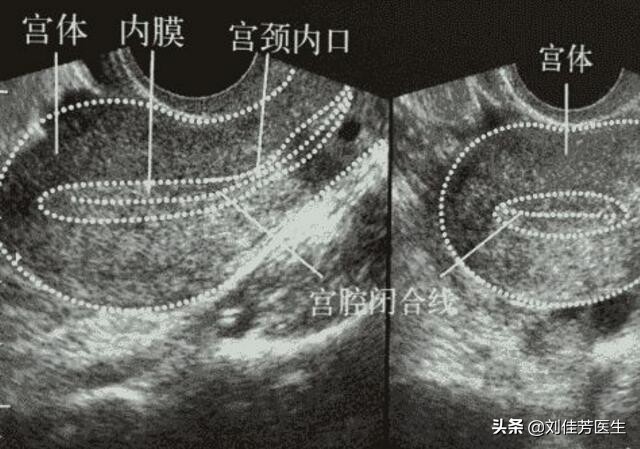

很多女性对于子宫内膜过厚,并没有十分清楚的概念。根据目前的医学观察来看,不同的个体之间,子宫内膜的厚度都有点不同。女性的子宫内膜厚度,会有一个周期性的变化。按照大多数人的子宫内膜变化情况来看,女性的子宫内膜最薄不会超过2毫米,最后不会超过10毫米。当女性的检查结果显示,子宫内膜厚度超过了10毫米的话,往往就可以算作是子宫内膜增厚了。